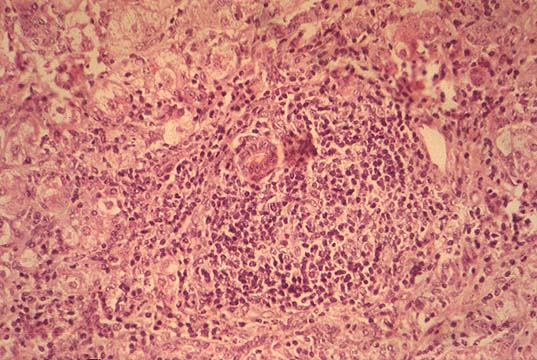

Fig. 119 - Portal

lymphocytosis.

Fig. 120 - Bile duct

lesion.

3--a strong lymphocytic infiltration of portal fields.

4--epithelial damage of portal bile ducts.